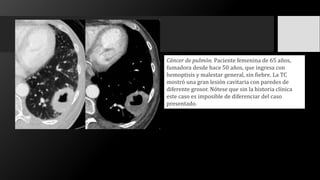

Cáncer de pulmón. Paciente femenina de 65 años,

fumadora desde hace 50 años, que ingresa con

hemoptisis y malestar general, sin fiebre. La TC

mostró una gran lesión cavitaria con paredes de

diferente grosor. Nótese que sin la historia clínica

este caso es imposible de diferenciar del caso

presentado.